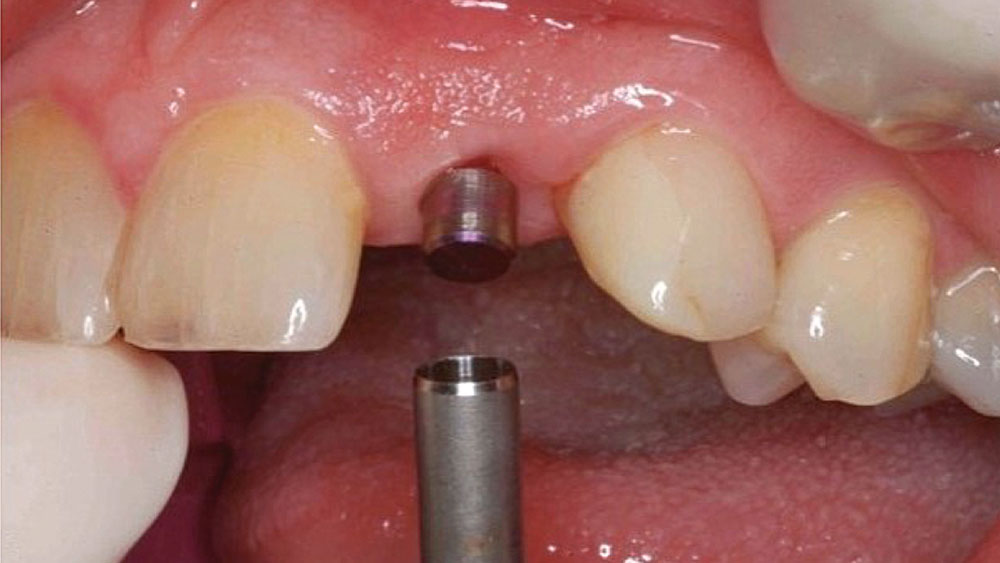

To achieve an optimal functional and esthetic outcome, the implant must be placed correctly with regard to trajectory, adjacent vital anatomy, and buccolingual, apicocoronal and mesial-distal positioning. Situating the implant so that the edges of the osteotomy are at least 2 mm from the buccal and lingual cortical plates, 2 mm from adjacent roots, 2 mm from vital structures, and 2–3 mm below the crest of tissue will keep the implant within the envelope of acceptability. The implant trajectory should emerge lingual to the incisal edge of the planned restoration, which allows for a screw-retained crown.

This case is an example of an ideal clinical situation for dentists who are new to placing implants in the esthetic zone. The patient requested treatment for a fractured upper lateral incisor. After extraction, grafting and healing, ample bone and soft tissue were present, and an implant was placed in optimal position for an esthetic result. The screw-retained restoration predictably restored form and function, illustrating the beautiful results that can be achieved by observing simple surgical and prosthetic guidelines.